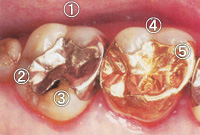

- ①保険の金属の詰め物

- ②段差ができています。

- ③段差にあたらしくむし歯ができてしまいました。

- ④ゴールドの詰め物

- ⑤段差がなくツルツル。プラークがたまらないため予後も良好です。